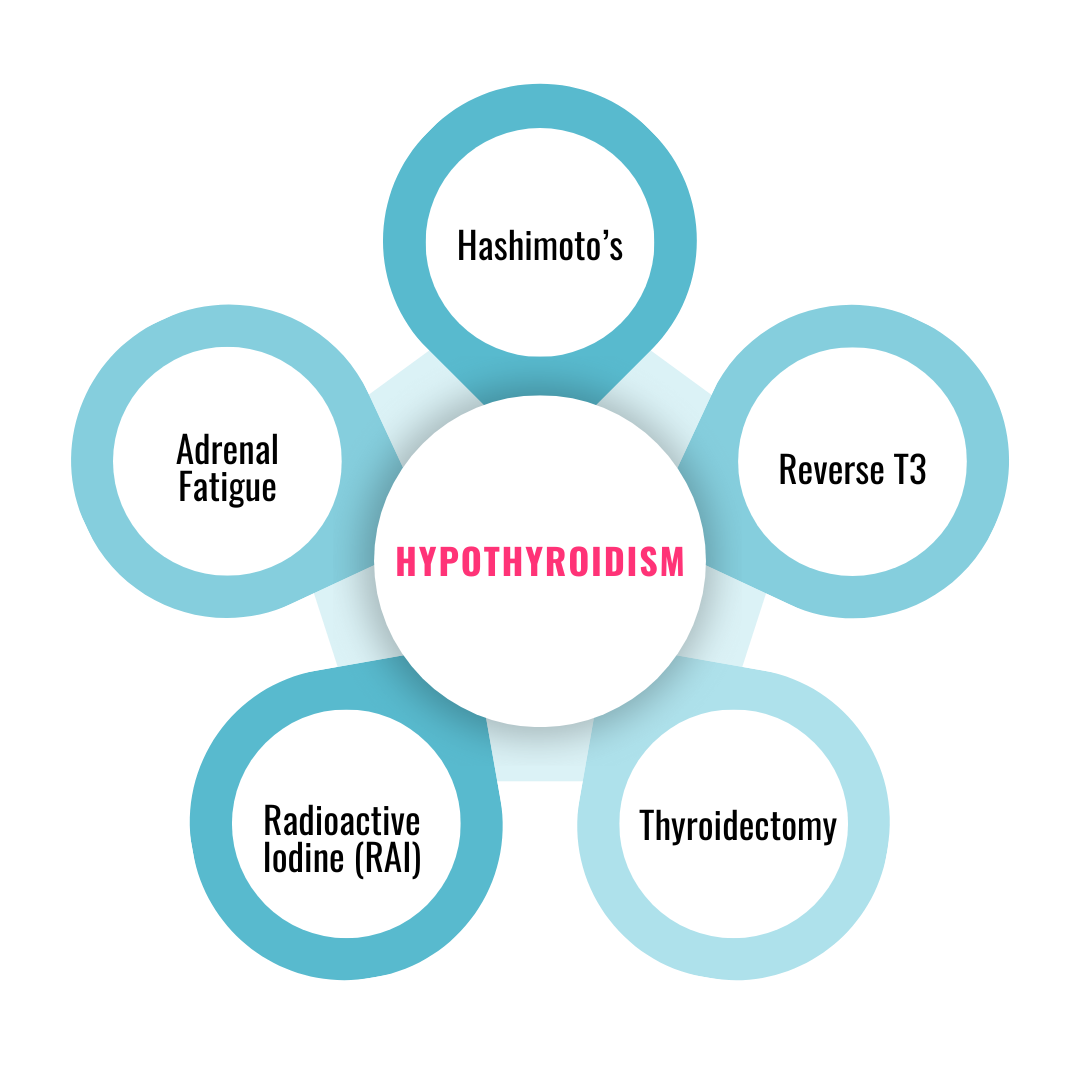

Who is this program for?

Anyone suffering with...

Hypothyroidism

Hashimoto’s

Reverse T3 problems

Post-Thyroidectomy Challenges

Post-Radioactive Iodine Challeneges (RAI)